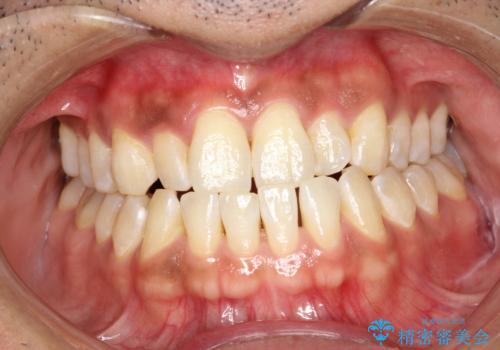

- 歯磨きの際に出血したり、口臭も気になるとのことで来院されました。PMTC30分コースにてクリーニングを行いました。

歯磨きの際の出血、お口の中の違和感・変化などを放置していると、のちに歯を失ってしまう原因になることもあります。

歯周病の原因は、口の中に棲む歯周菌です。歯周病菌や歯周病菌の出す毒素が引き起こす炎症によって歯茎が腫れ、歯を支えるセメント質、歯槽骨や歯根膜が破壊されて、ついには支えを失った歯が抜けてしまうという怖い病気です。